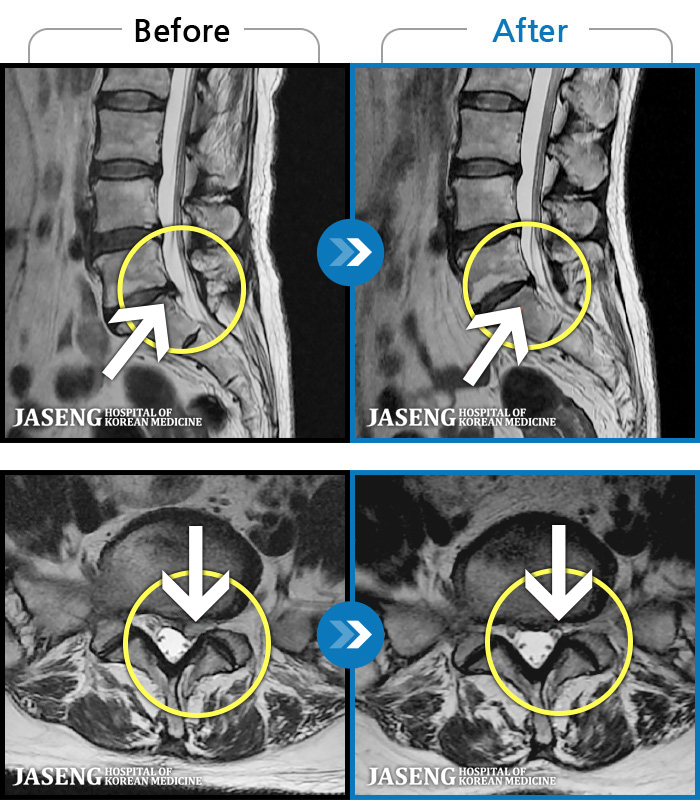

1,228건의 MRI 전후 사진으로 터진 디스크 흡수 사례를 확인하세요.

※ 환자분에게 사전 동의를 받아 동일 조건에서 촬영되었으며, 개인에 따라 치료 후 부작용이 발생할 수도 있으니 사전에 의료진과 상담 후 치료를 진행하시기 바랍니다.